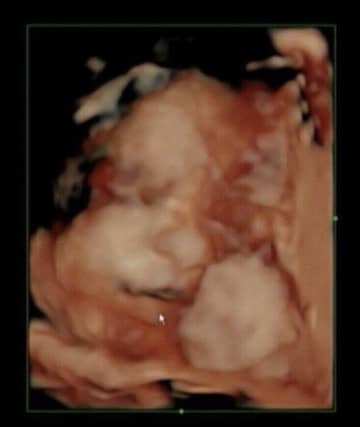

妊娠41週で無痛分娩での出産。なぜか夫が横でラマーズ法の呼吸を【たまひよ 出産体験談】